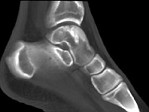

- 单项选择题男,17岁, 踝关节疼痛,关节作响, 结合图像,最可能的诊断是 ( )

B、剥脱性骨软骨炎